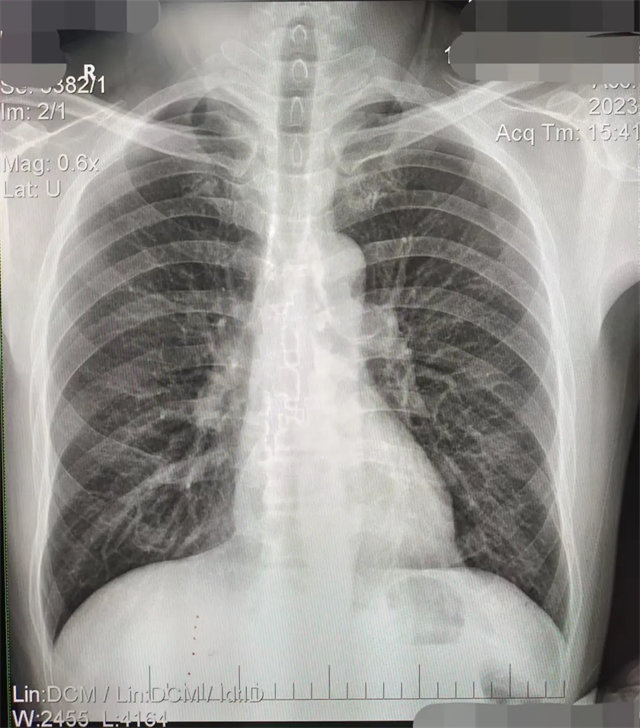

缺陷:左肩胛骨部分與左肺野重疊。

解決:使患者左肩旋前緊貼成像件重新曝光。

缺陷:肩胛骨未完全拉離肺野,吸氣不完全,存在金屬偽影遮擋,略有聳肩,且肺尖顯示不好,圖像顆粒感較強(qiáng),管電流量不夠,信噪比偏低。

解決:去除金屬物品后,按標(biāo)準(zhǔn)體位,使患者雙肩旋前與前胸一并緊貼成像件,適當(dāng)調(diào)高mAs,然后深吸氣后屏氣曝光。